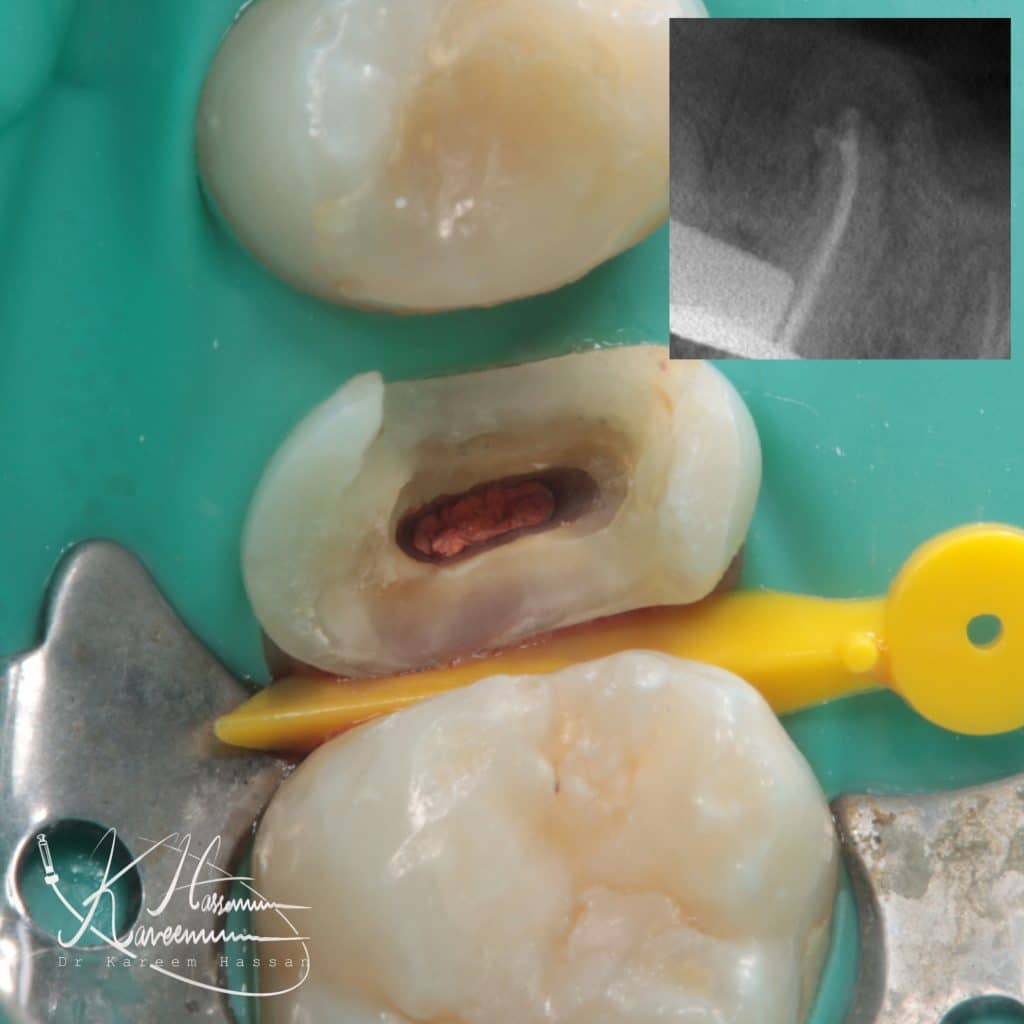

Female patient with destructive second premolar

-remove amalgam restoration and cleaning..

-isolation

-RCT with bio-c sealer(one-fill) and hydraulic technique

Obturation with bio-c sealer